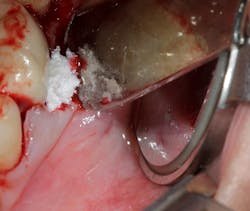

Technology solution: Commercially available bone grafts, such as Geistlich Bio-Oss Collagen, can have components that make them space maintaining as well as act as polymers to absorb and release growth factors and proteins (figure 5). By adding growth-stimulating factors/proteins to your regular bone grafts (figure 6), an increase in osteopromotive potential occurs that can have the ability to overcome a deficiency of bone walls.9 In other words, your bone graft can become alive, and furcations that once were unable to be repaired (figure 7) now have a more predictable success rate10 (figure 8).